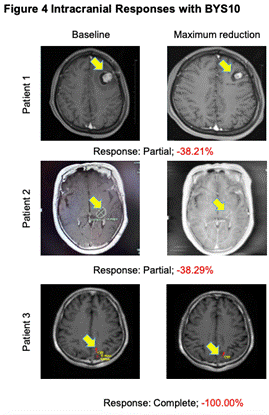

йЂШжХИеЕ•иДСпЉЪBYS10еМїж≤їдЉіиДСиљђзІїRETз™БеПШеЃЮдљУзШ§еЃЮзО∞йҐЕеЖЕзЉУиІ£

йТїз†ФдЇЇеСШеЬ®4дЊЛиЗ≥е∞СжЬЙ1дЄ™еПѓдЄИйЗПйҐЕеЖЕзЧЕзБґпЉИ1дЊЛйҐЕеЖЕйљРеЕ®зЉУиІ£пЉЙзЪДжВ£иАЕдЄ≠иІВеѓЯеИ∞йҐЕеЖЕжКЧиВњзШ§жіїжАІ����гАВ

еЫЊ4.йҐЕеЖЕжКЧиВњзШ§жіїжАІ